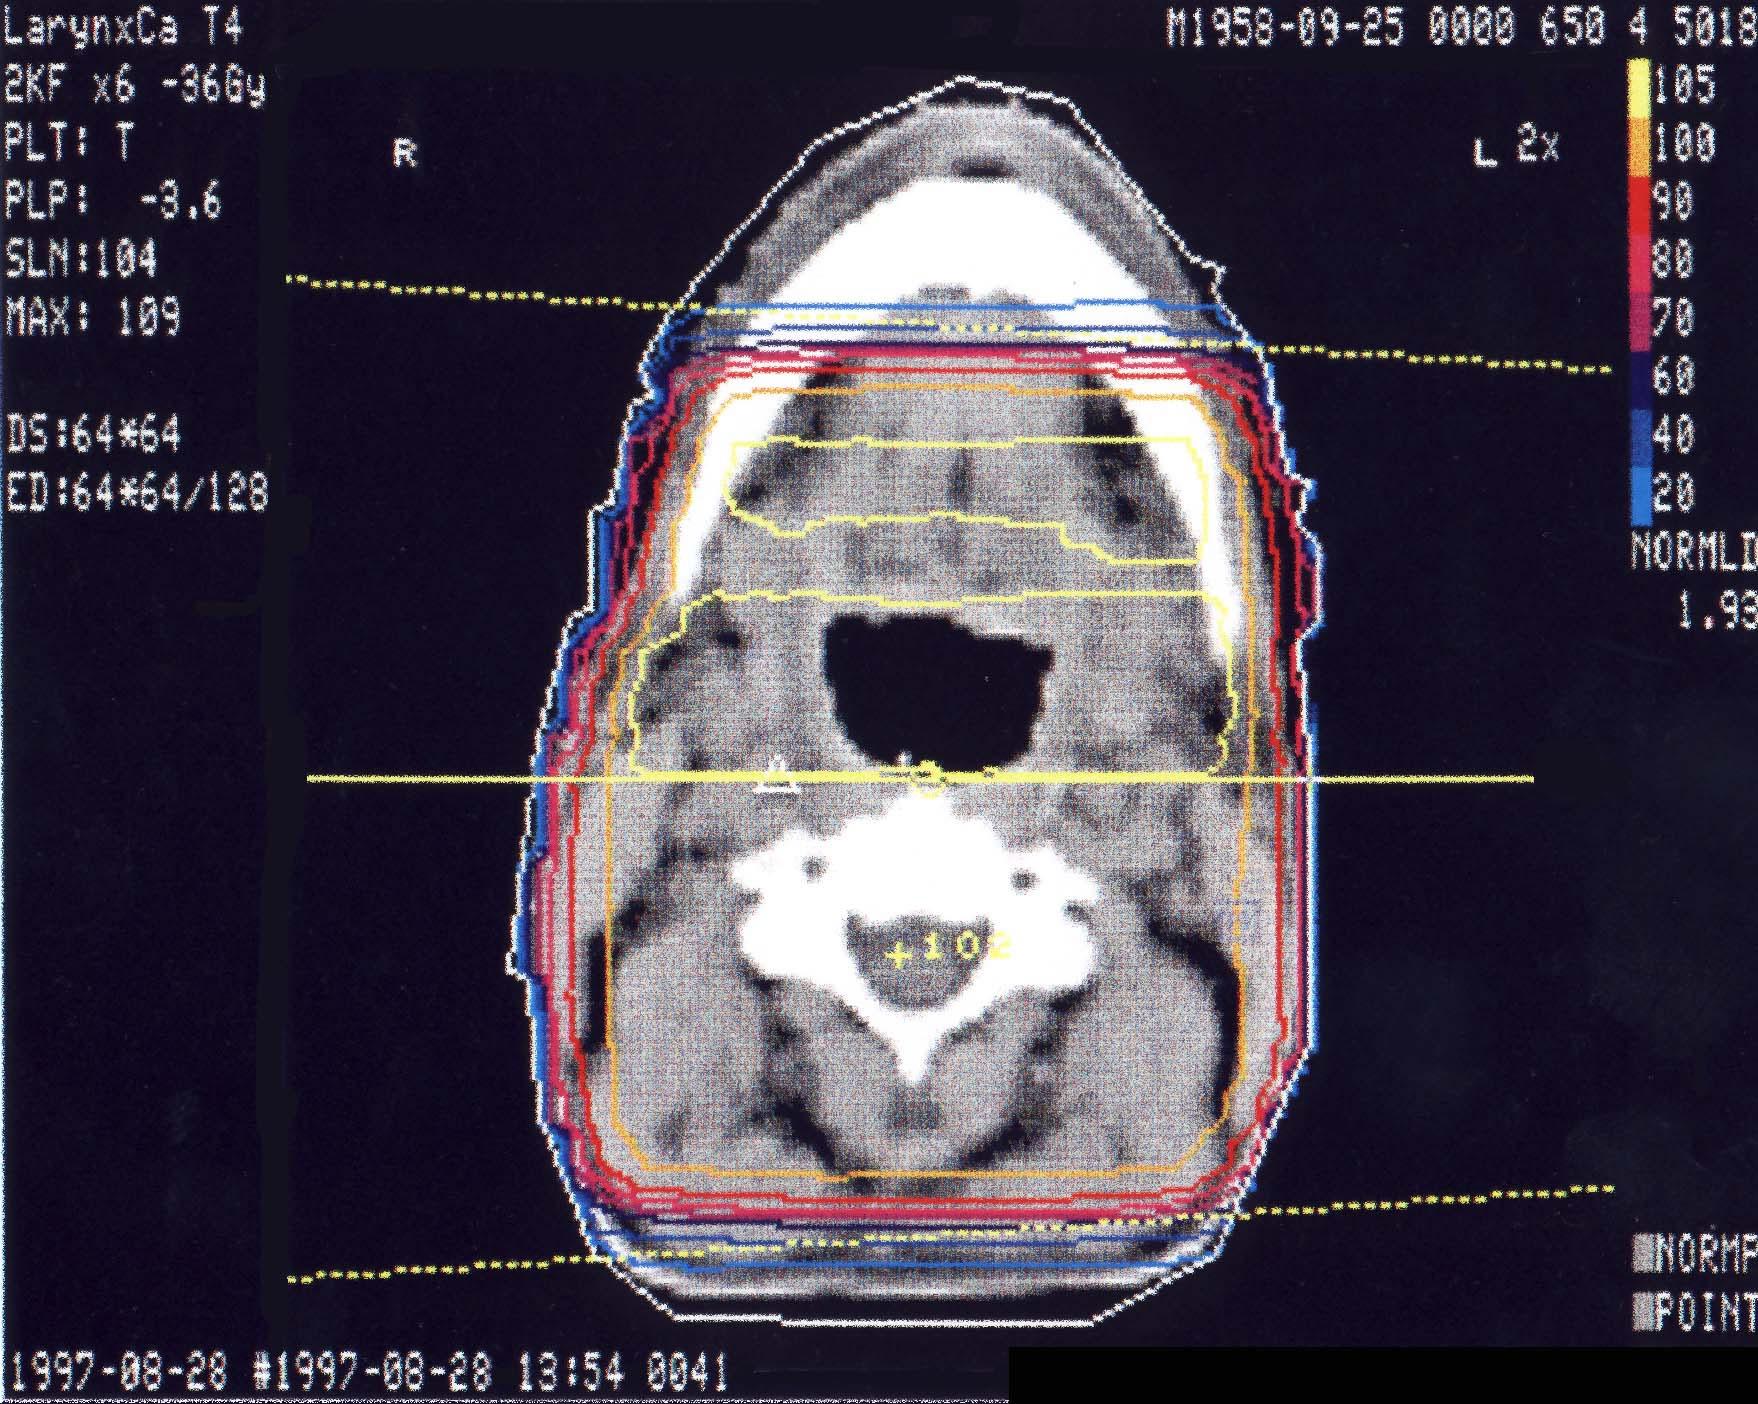

HNO-Karzinome: Bestrahlungsplan

Einführung aktuelle Bilder - Einführung Bestrahlungspläne - Einführung Demonstration